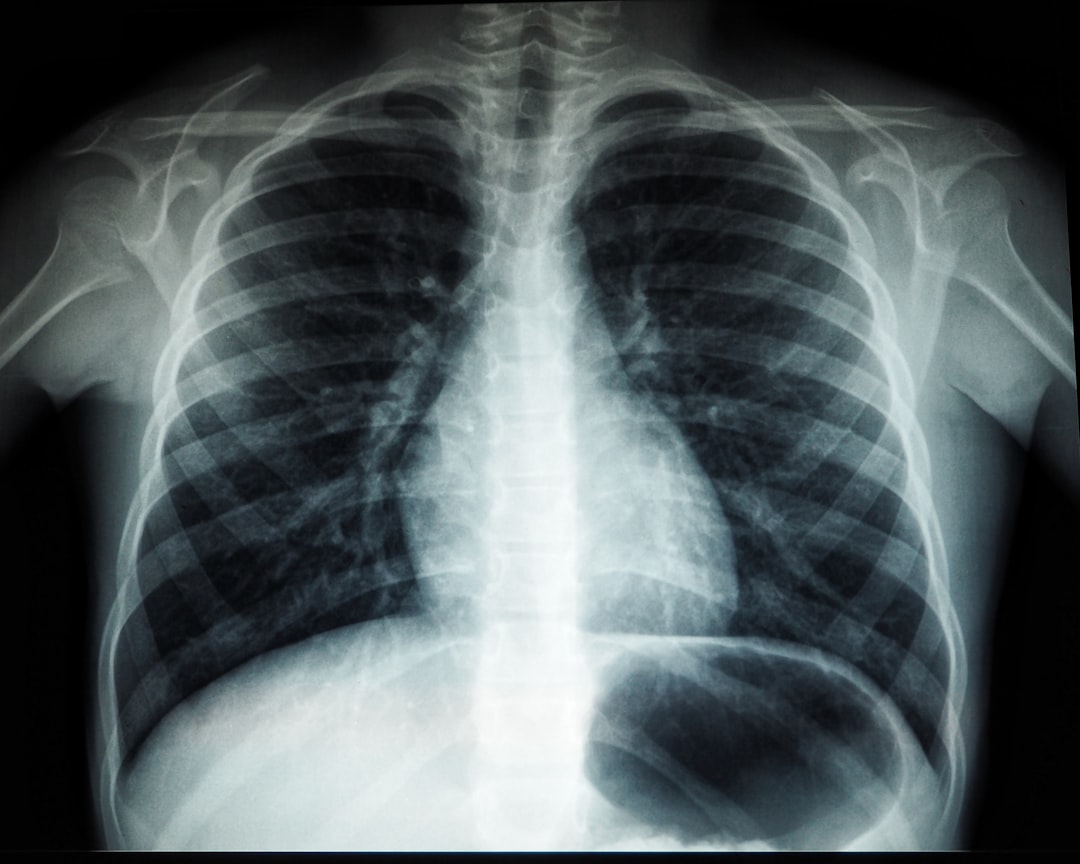

겨울철은 호흡기 질환이 증가하는 시기입니다. 추운 날씨와 낮은 기온은 우리 호흡기를 위협하는 주요 요인 중 하나입니다. 이때 날씨가 추워지면 사람들은 대개 실내에서 시간을 보내게 되며, 밀폐된 공간에서 쉽게 전파되는 바이러스와 세균에 노출될 가능성이 높아집니다. 이러한 요인들은 호흡기 질환 종류의 발병을 촉진하므로, 주의가 필요합니다.

특히, 만성 하부호흡기 질환을 가진 환자들은 일반 인구에 비해 더 위험합니다. 이들은 연령, 기존 질환 등 다양한 요인으로 인해 호흡기가 약해져 겨울철에는 더 많은 주의를 기울여야 합니다. 감기나 독감과 같은 일반적인 바이러스 감염도 호흡기 질환으로 발전할 수 있으므로, 적극적인 관리가 필수적입니다.

호흡기 질환의 증상은 다양합니다. 기침, 가래, 호흡 곤란 등으로 나타나며, 심하면 고열과 함께 일상 생활에 큰 지장을 줄 수 있습니다. 만약 이러한 증상이 나타난다면 즉시 병원을 찾는 것이 중요합니다. 또한, 조기 치료는 합병증 발생을 예방하는 데 큰 역할을 합니다.